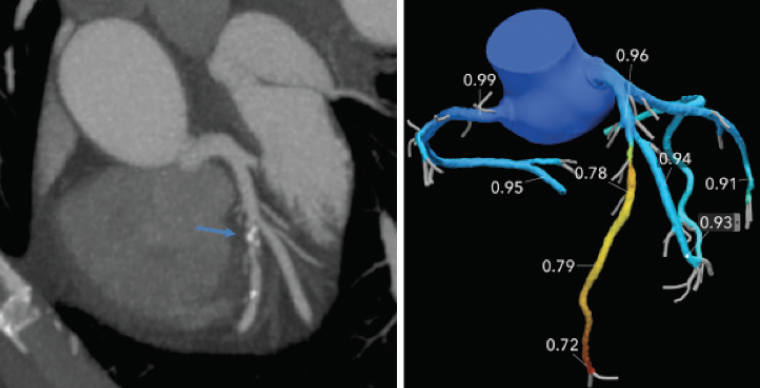

Figure 1. A 68-year-old man with atypical chest pain who underwent CCTA to exclude CAD was found to have a moderate (50%–69%) stenosis in the mid-left anterior descending artery. The lesion was uploaded for FFRCT analysis, which documented borderline lesion-specific ischemia with FFRCT value of 0.78.

Despite the ongoing improvement in image quality, diagnostic accuracy, reduction in radiation dose, and increasing clinical utility, patients are more likely to undergo invasive coronary angiography (ICA) after CCTA than patients evaluated with upfront stress testing. In the PROMISE trial, in which more than 10,000 patients were randomized between CCTA and traditional stress testing, 12.2% of patients in the CTA arm underwent ICA versus 8.5% in the stress testing arm. Despite this higher rate of ICA in the CTA arm, the rate of nonobstructive disease was significantly lower at 28% versus 52% in the stress testing arm (P < .001) (Figure 1).2